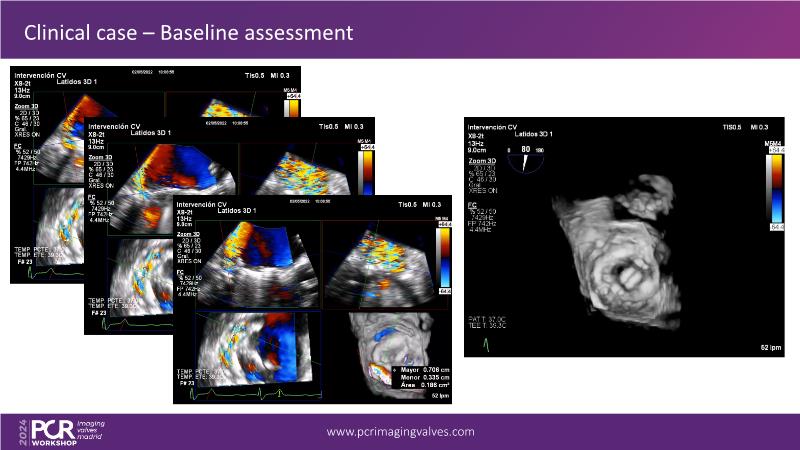

Explore cutting-edge transcatheter valve interventions for mitral and aortic valve disorders, including valve-in-valve procedures and management strategies for paravalvular leakages, and learn about diagnosing and treating mitral annular calcification and transcatheter options in infective endocarditis.

- To get tips and tricks for guidance of transcatheter intervention